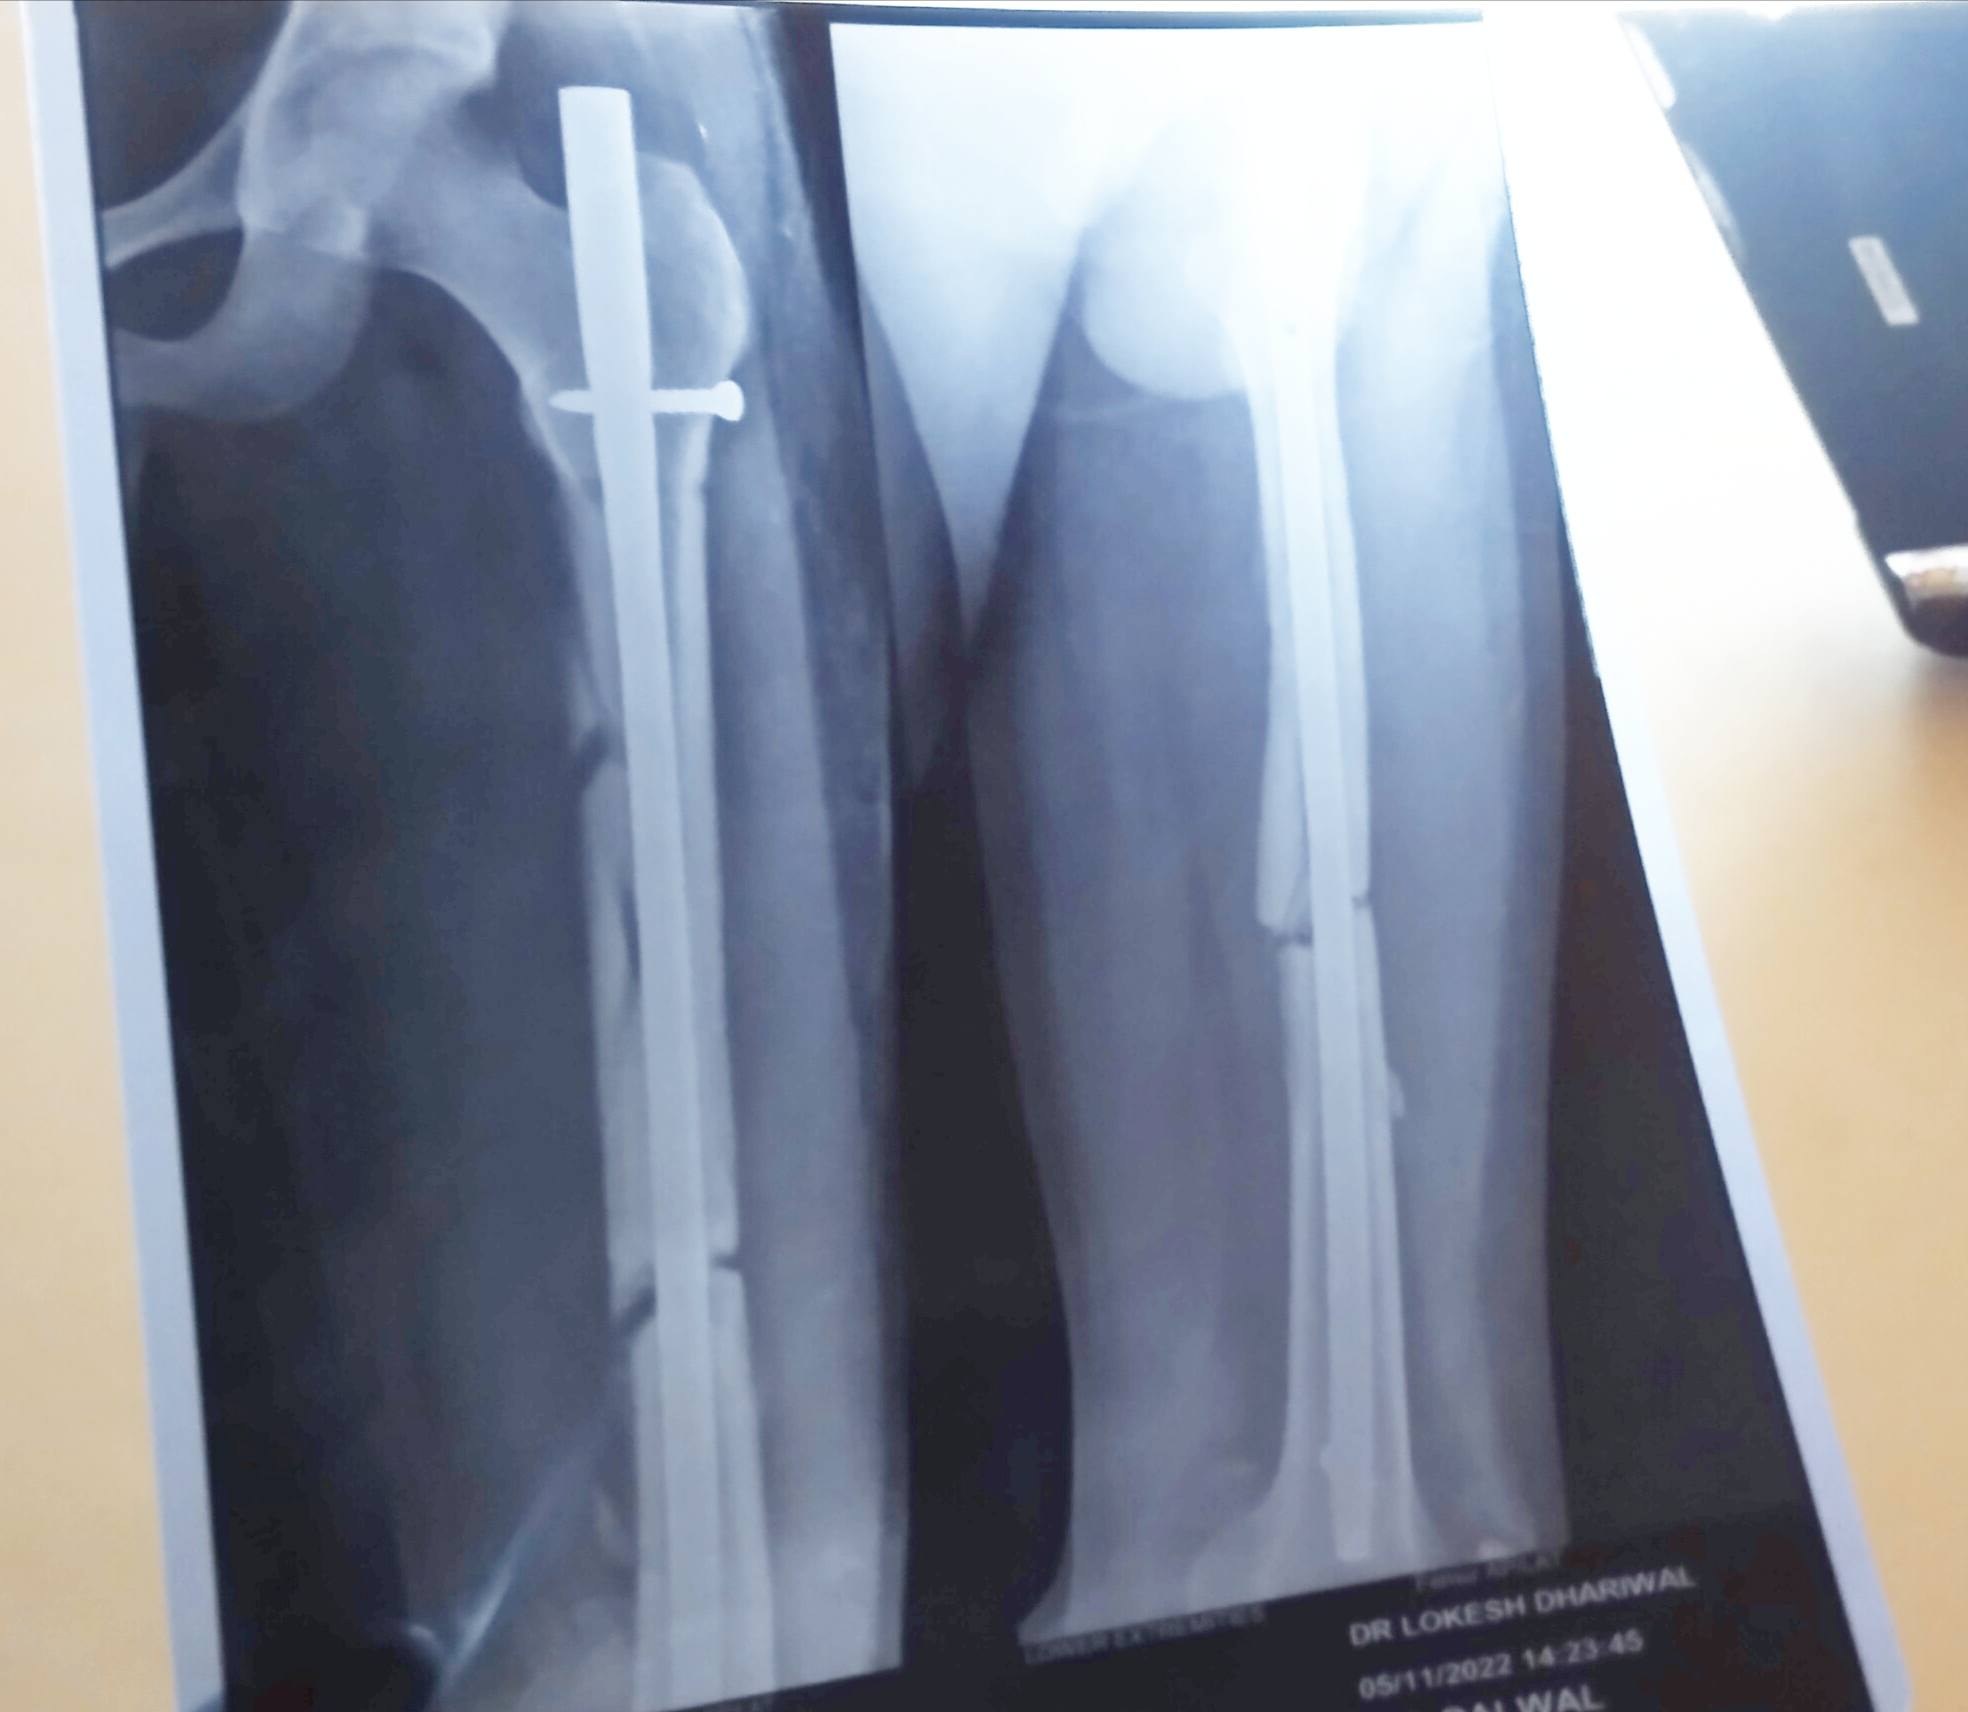

Dushyant from palwal

Sir m ek cheej janna chahta hu ki mujhe femoral shaft displaced fracture hua tha vo bhi closed.mujhe 3 mhine ho chuke hn ab mujhe koi pain nahi hota.

1.mujhe kab tk ye limping ka chhkr rhega

2.Aur sir mujhe aalti paalti maarte hue bhi koi pain nahi hota sidha khde hone m bhi koi pain nahi hota

Apke experience se sir its sign of bone unite or not ?

abhee isme kuch months lagenge